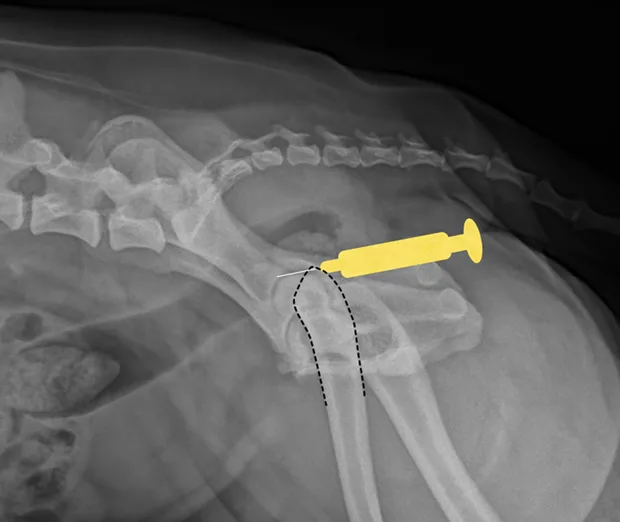

Shoulder

Place the patient in lateral recumbency with the shoulder joint in a neutral position. For large dogs, insert the needle about 0.5–1 cm distal to the acromion process of the scapula in a lateral-to-medial direction; a lateral radiograph of the shoulder joint may help determine the distance from the distal acromion to the joint space. The needle may need to be passed in a slightly dorsal direction to enter the joint. A 1.5-inch needle is adequate for even large-breed dogs.

Craniocaudal view of shoulder. Place needle just distal to the acromion (yellow dot), angled slightly dorsally.

Lateral view of shoulder. Insert needle just distal to the acromion (yellow dot).